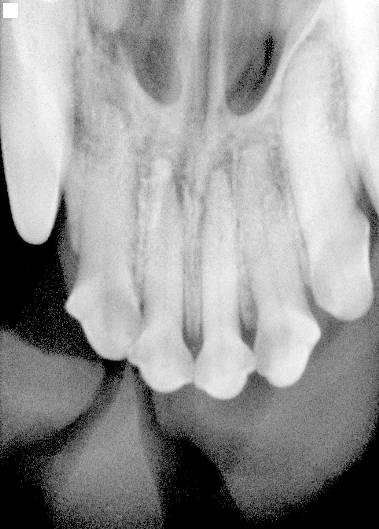

Left: Knuckle's mouth Right: Bridey's upper incisors

Bridey's upper 4th premolar... OUT it goes.......